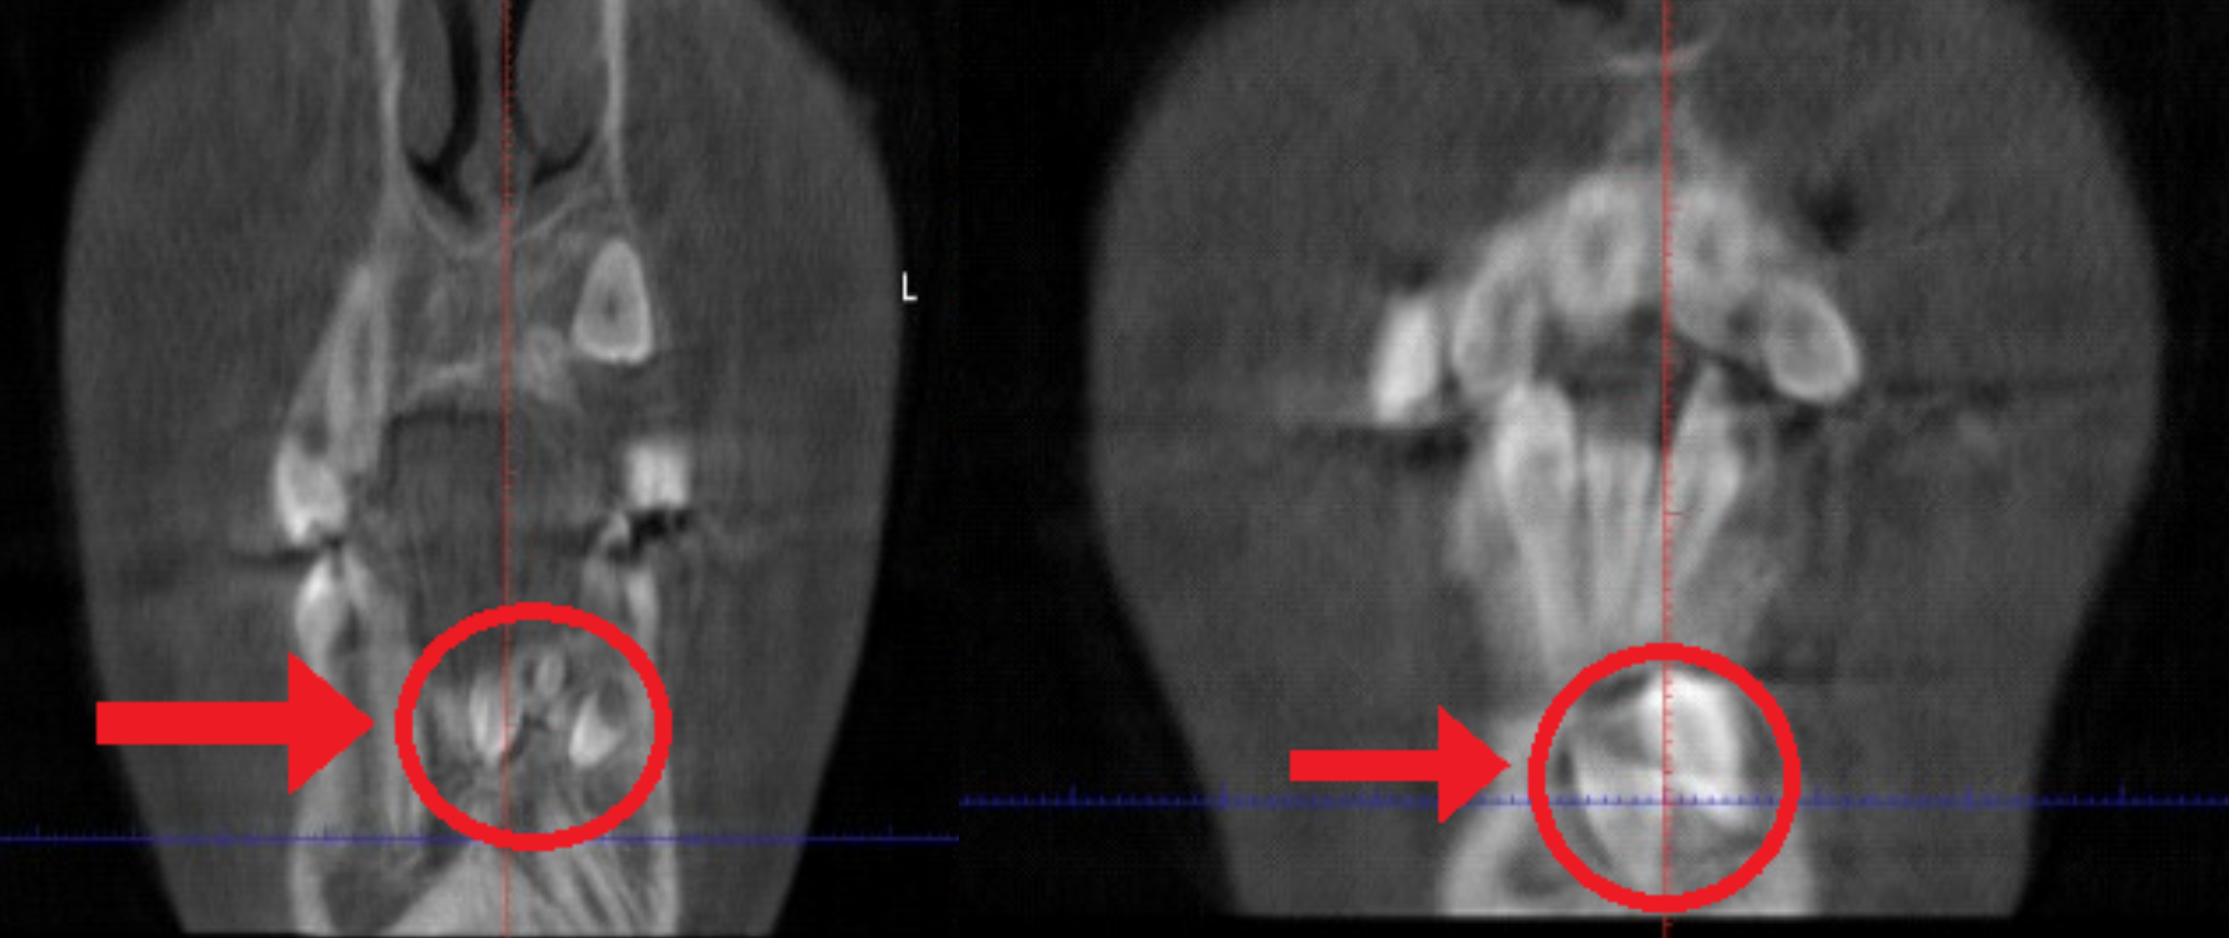

This case includes a panoramic X-ray and two segments of a CBCT (cone beam x-ray) images that highlight the importance of early screening. This patient’s permanent lower canine was unable to erupt because extra teeth were blocking its path. By identifying the problem early and removing the extra baby teeth, we were able to clear the way for the permanent tooth to come in naturally—preventing more complex treatment later.